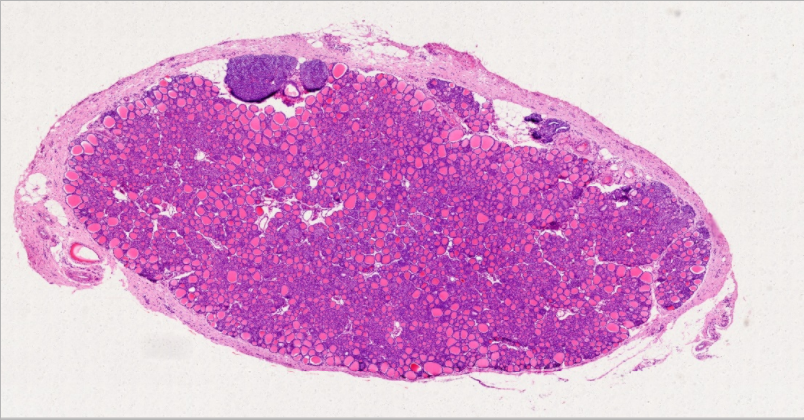

弥漫性非毒性甲状腺肿:甲状腺滤泡明显扩张,内含大量胶质,滤泡上皮细胞受压呈扁平状。部分上皮增生,可见小滤泡和小假乳头形成。

1.全景图

![]()

2.纤维组织包膜

3.滤泡上皮增生

4.滤泡扩张